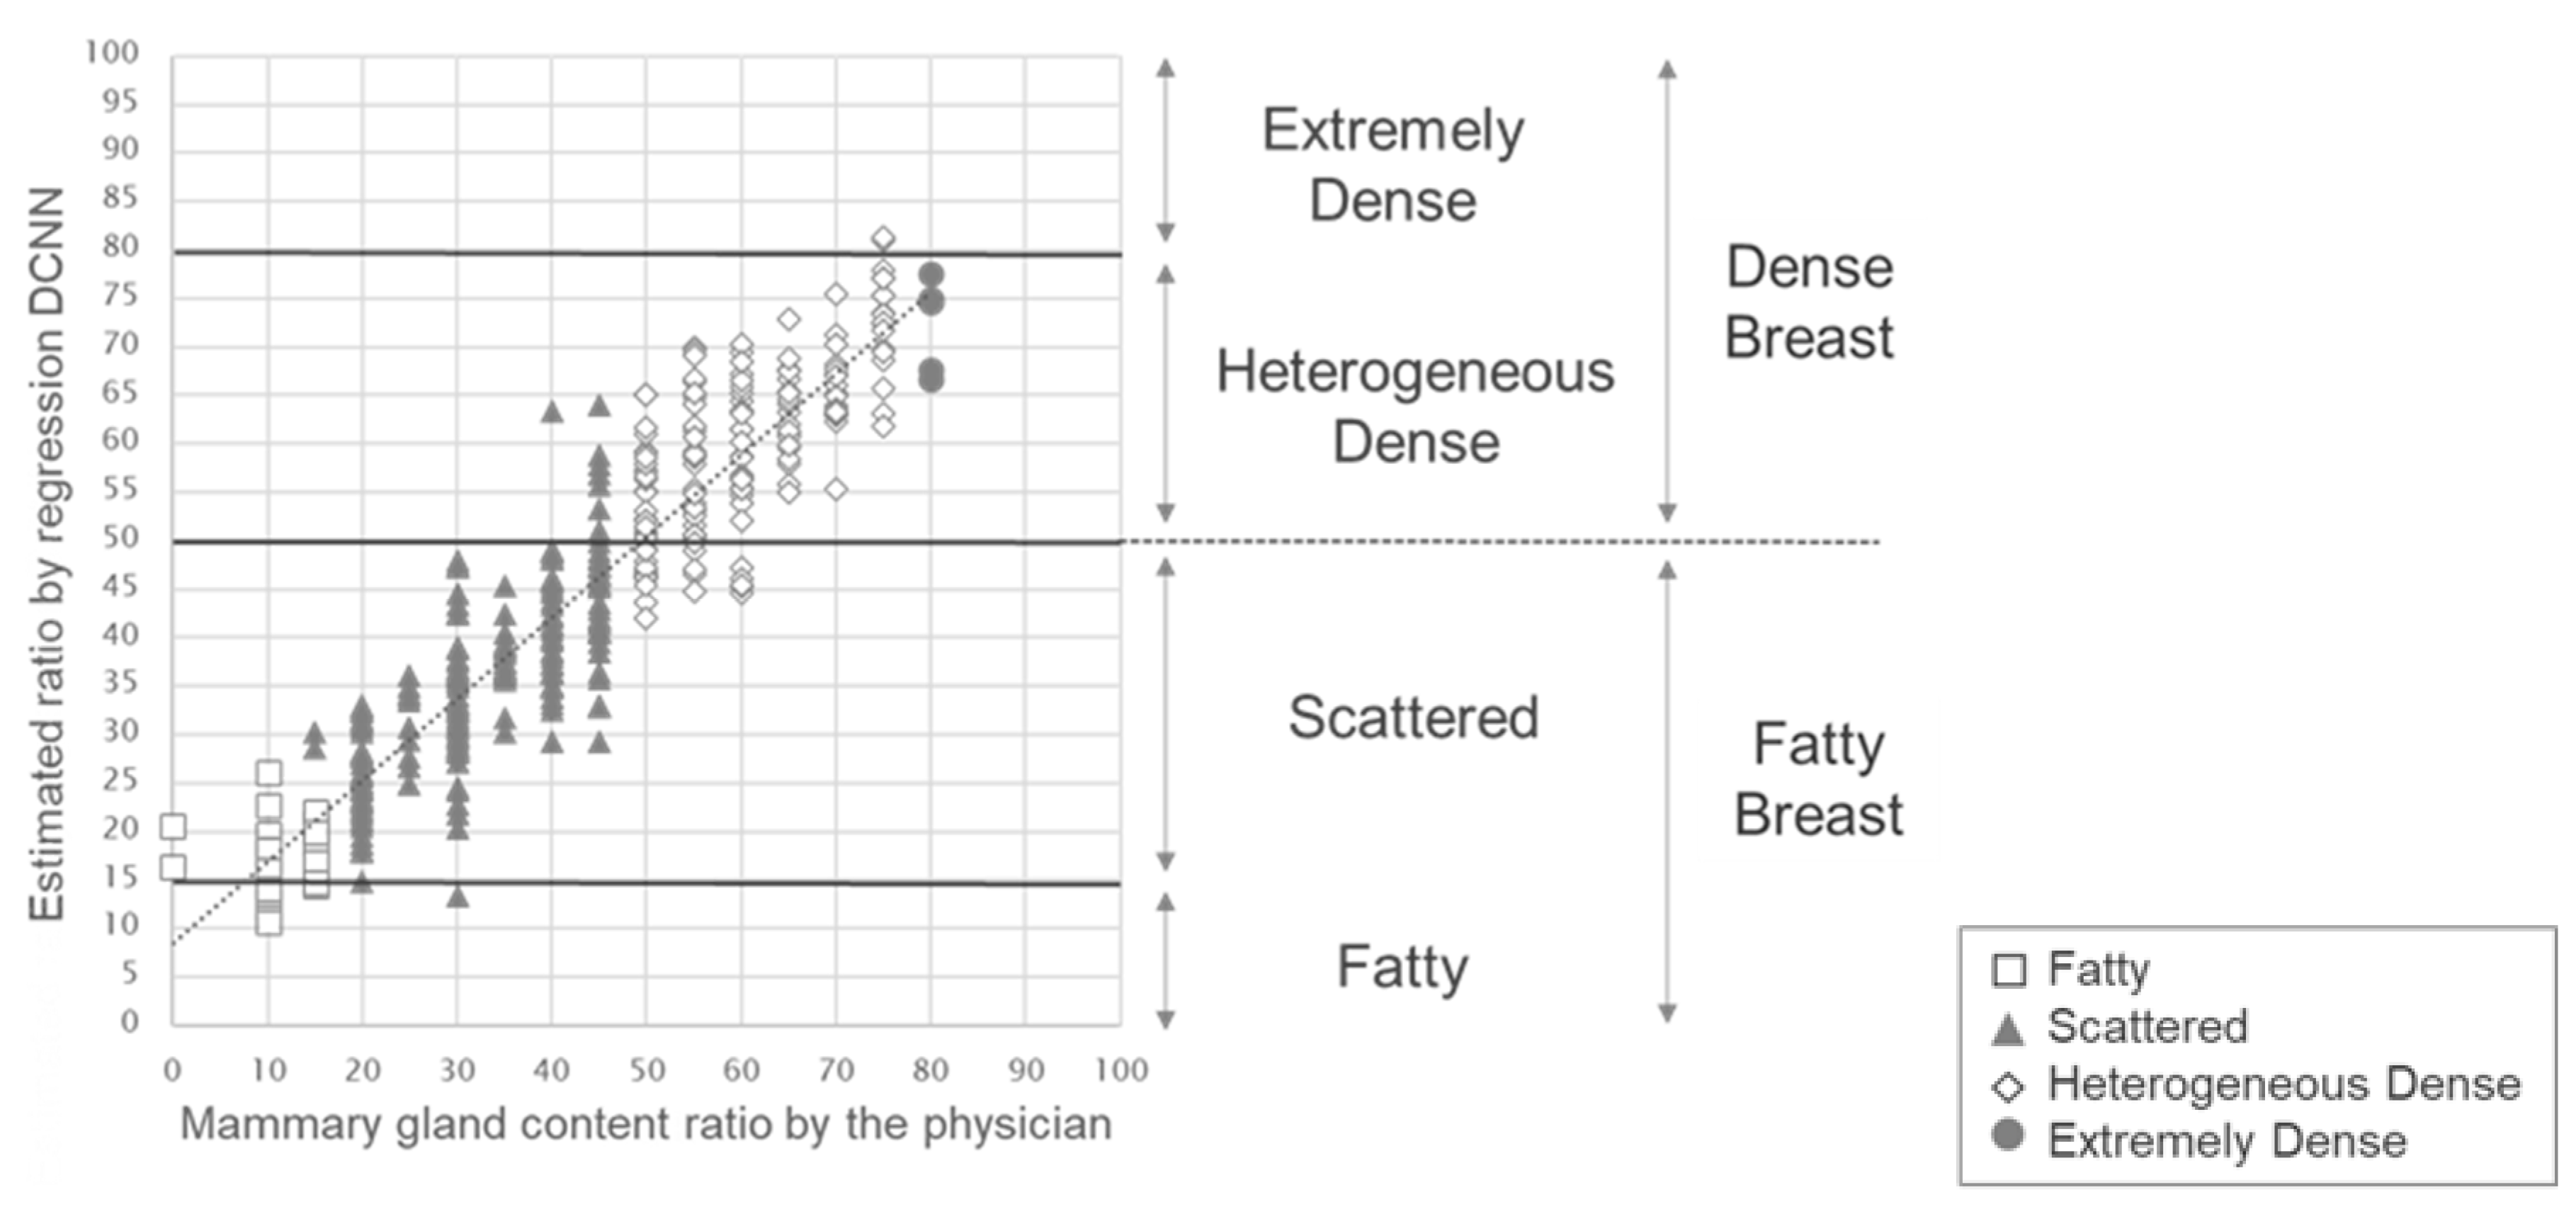

3. Results

4. Discussion